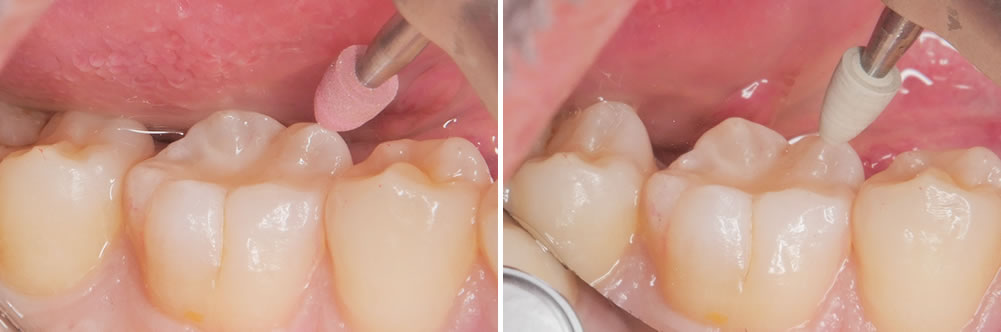

酸処理

内部の虫歯を取り除いた状態です。接着力を上げるため酸処理を行いました。

接着処理

酸処理後には接着処理を行います。

CR充填

コンポジットレジンという樹脂の材料を用いて削った部分を埋めていきます。

形態を整えて歯の形にしていきます。

治療完了

形態修正と研磨を行い、治療が終わりました。